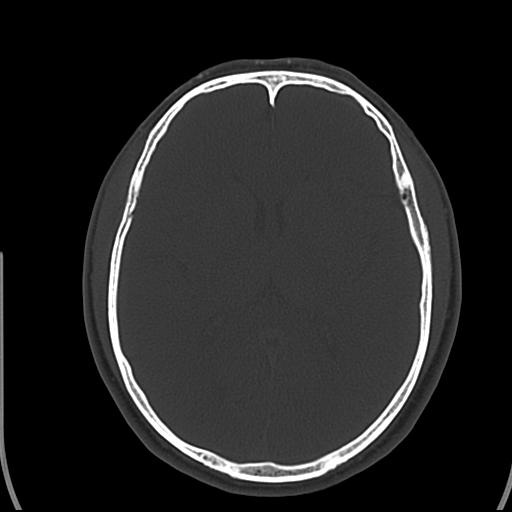

头皮下高密度结节影???临床上在老年男性比较常见。大家看看是什么?成因是? 本例患者,男性,51岁。外伤来诊。无染发史及发根植入史。

考虑异物。

皮下钙化点

没见过,可能为毛囊钙化。